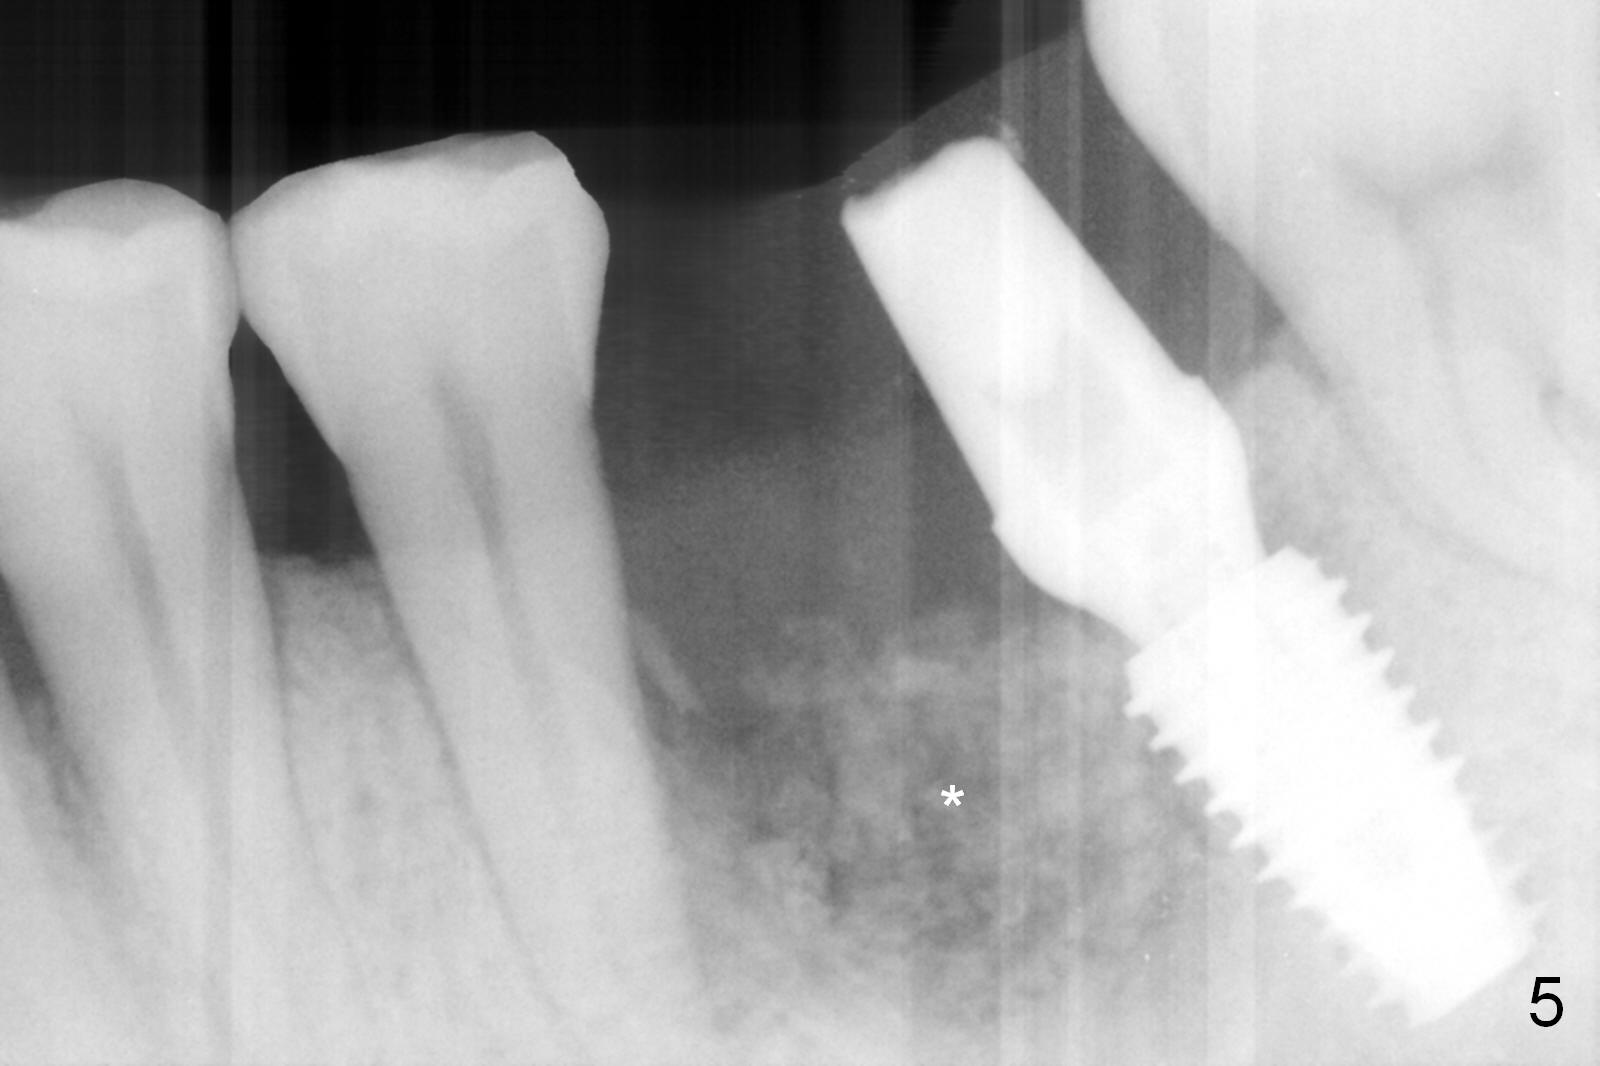

Considering the severe bone loss in the meisal socket, socket preservation is indicated if immediate implant is not feasible. Preop exam shows that the mesiobuccal gingival recession (Fig.1 MB) is not as severe as the mesiolingual one (Fig.2 ML). Because of oozing from the mesial socket, buccal envelop incision is made with flap raising to increase visibility. Probably due to periodontal infection, pain control is difficult. Osteotomy buccal to the Inferior Alveolar Canal proves to be risky. In addition, osteotomy in the mesial socket is more difficult than the distal one (Fig.3). Once the osteotomy depth is determined relative to the superior border of the Inferior Alveolar Canal (4 mm), the osteotomy depth increases by 2 mm. A 5.5x10 mm implant is placed with insertion torque ~ 35 Ncm (Fig.4); a 15 ° angled abutment (5.5 mm in diameter, 4 mm in cuff) is placed mesially. Then the abutment is turned lingually favorable for restoration (Fig.5), the remaining socket is filled with allograft/Osteogen (*) and Collagen Plug.